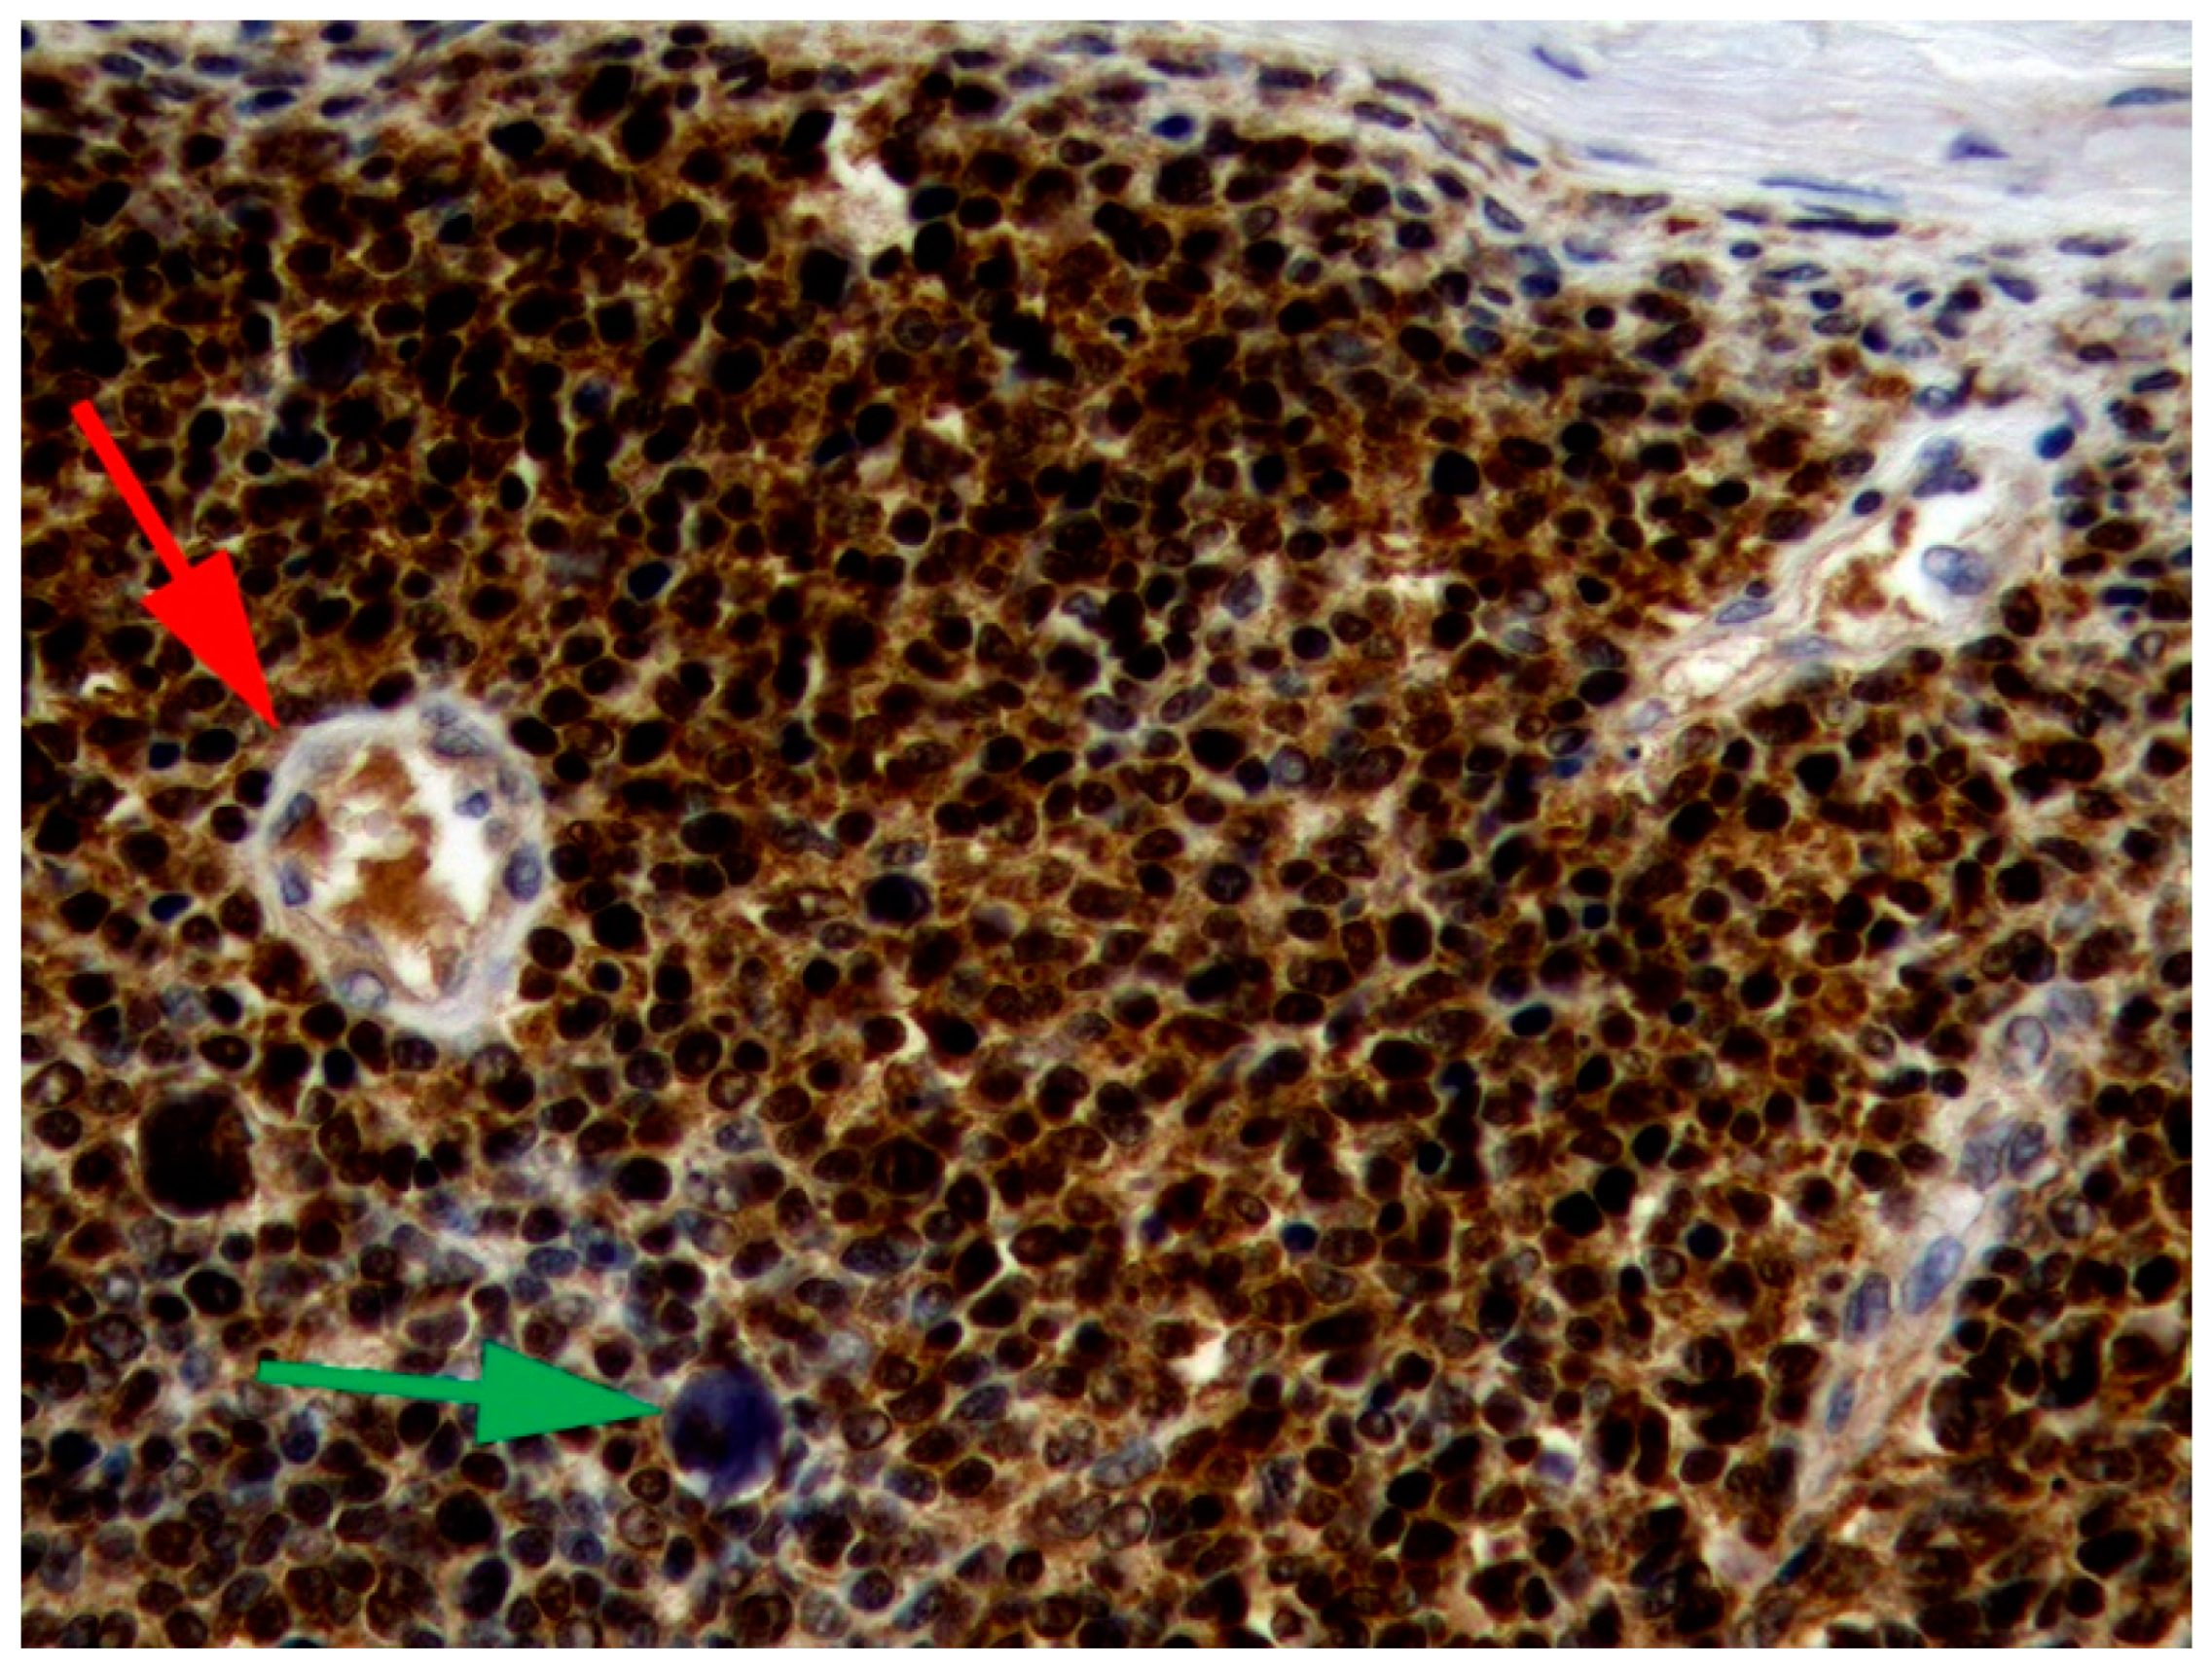

6.2. Canine Viral Cutaneous Plaques

6.3. Papillomavirus-Associated Neoplasia in Dogs